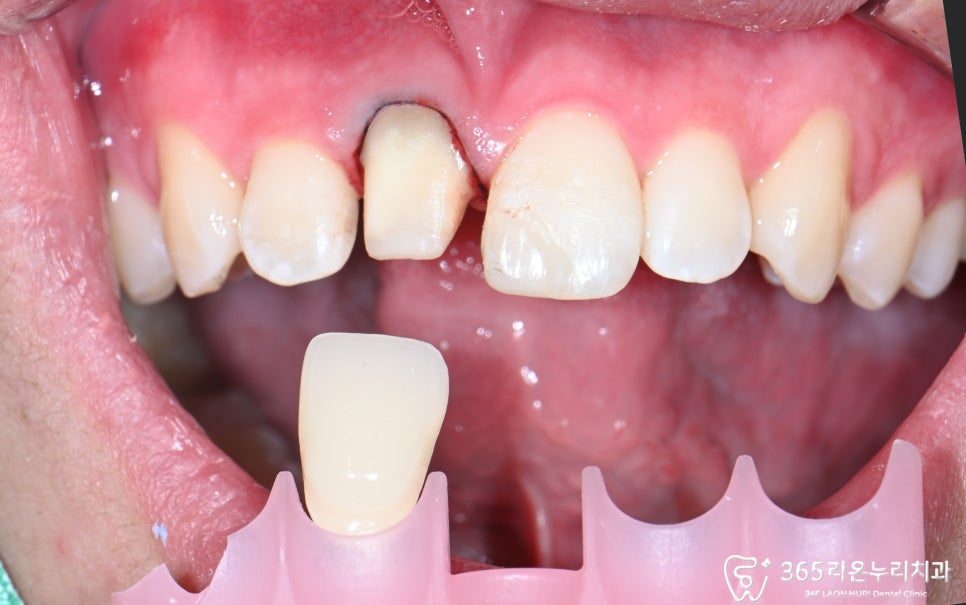

색상(쉐이드) 확인

최종 보철물이

인접치와 자연스럽게 어우러질 수 있도록

쉐이드(색) 확인 과정도

꼼꼼히 진행해야 됩니다.

2025. 06.16

최종 보철 장착

마지막 단계로, 미리 확인한 쉐이드대로

인접치의 색에 맞춘 최종 크라운을

장착하면 마무리가 됩니다.

2025. 06.23